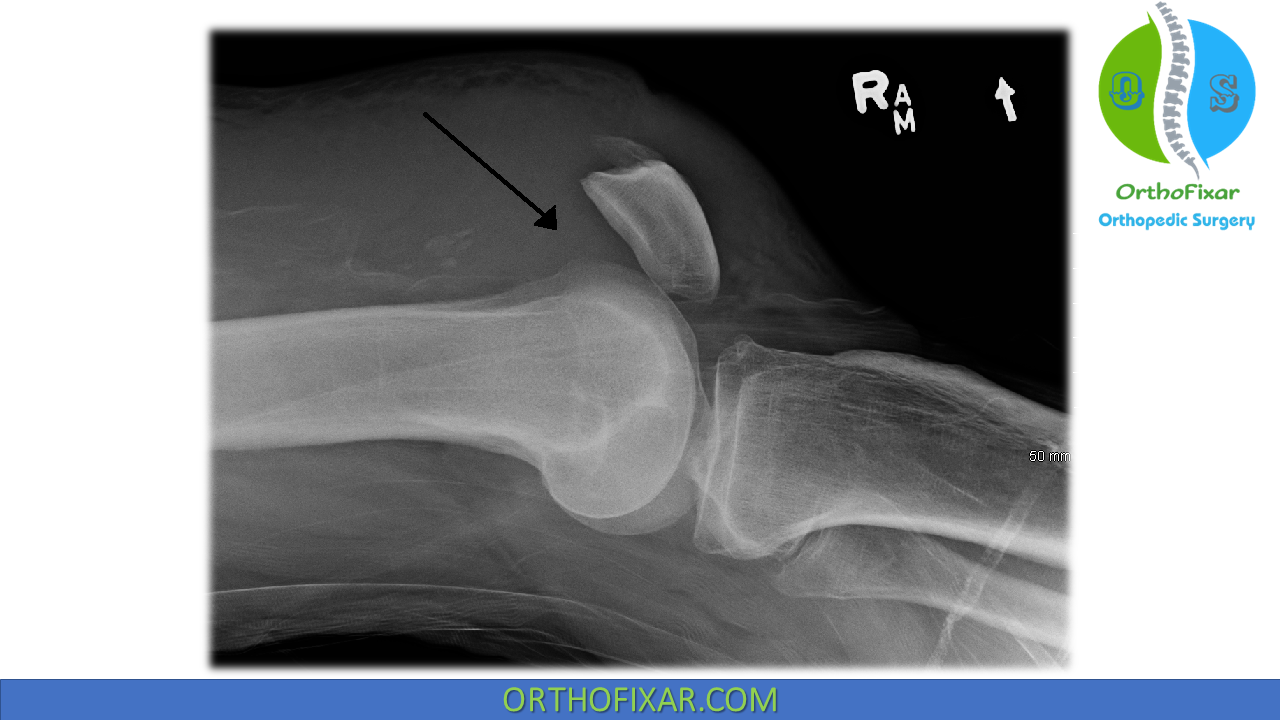

Парциальный разрыв мышцы

Парциальный разрыв мышцы 116 фото